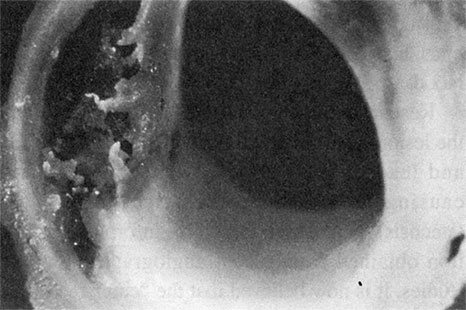

Разрастание атеросклеротических бляшек – тревожный симптом. По мере увеличения они имеют свойство разрываться (см. рис. 1.7а). Ранее ученые считали, что с большей вероятностью отрываются те бляшки, которые сильнее выдаются в просвет сосуда, т. е. вызывают более высокую степень стеноза (сужения) сосуда. Сейчас известно, что наиболее частой причиной коронарных событий являются нестабильные бляшки: они сужают просвет сосуда всего на 30–50 %, но при этом их липидное ядро окружено лишь тонким слоем соединительной ткани (см. рис. 1.7б). У многих людей с атеросклерозом имеется несколько бляшек с меньшей степенью стеноза. Бляшки, сужающие просвет сосуда на 70–90 %, встречаются относительно редко, но всегда угрожают повышенным риском неблагоприятных последствий (см. рис. 1.7в).

Рисунок 1.7а. При разрыве бляшки ее содержимое попадает в кровь и вызывает образование тромба в сосуде. Снимок предоставлен доктором Майклом Дж. Дэвисом